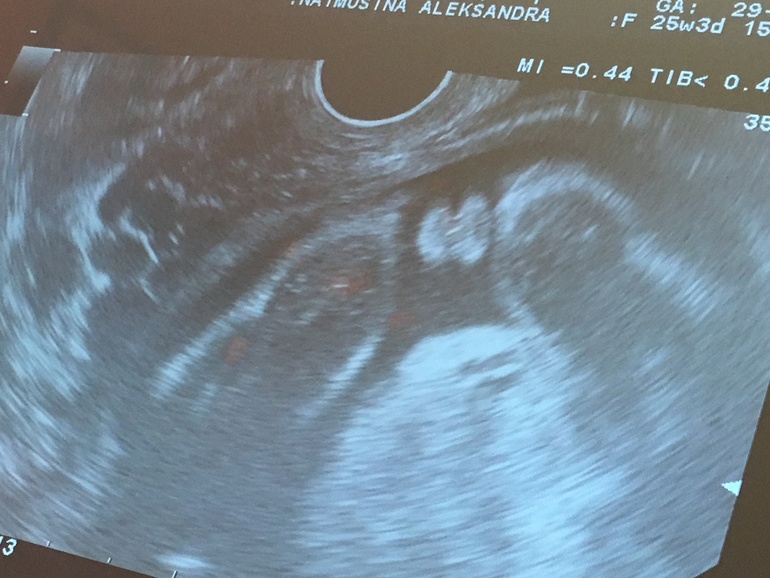

помогите разобрать узи

УЗИ, КТГ, доплерДевочки. Была на узи в 17 недель, помогите найти на фото, доказательство что это девочка)))

Девчачий пирожок, таких я уже 4 раза видела))) это девочка, в 17 недель у мальчиков там все торчком.

Вот где написано "девочка", справа. Снимок сделан снизу, как я думаю.

Да, фото конечно не лучшее... А есть вид "в профиль"? Не хочу расстраивать, но у меня снизу тоже на девочку было похоже. А как сбоку посмотрели, так сказали что мальчик...

фото только это, что девочка сомнений нет, она со всех сторон это продемонстрировала)))а вот фото понять не могу))чтобы мужу показать))

По фото ничего не видно. Лучше сходите еще раз на УЗИ попозже. Так и убедитесь.